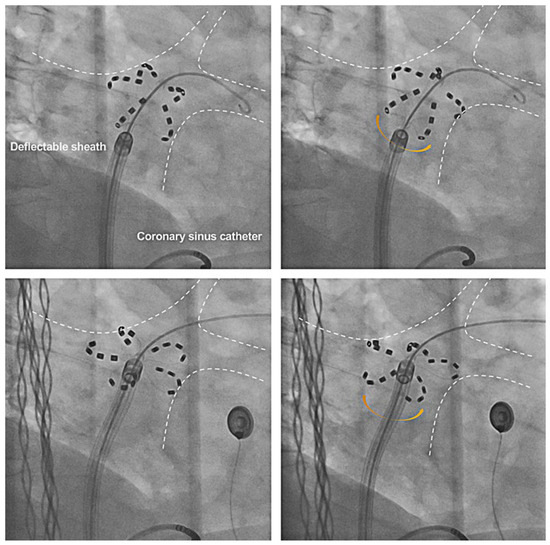

- Kueffer, T.; Madaffari, A.; Thalmann, G.; Mühl, A.; Galuszka, O.; Baldinger, S.; et al. Eliminating transseptal sheath exchange for pulsed field ablation procedures using a direct over-the-needle transseptal access with the Faradrive sheath. Europace 2023, 25, 1500–1502. [Google Scholar] [CrossRef]